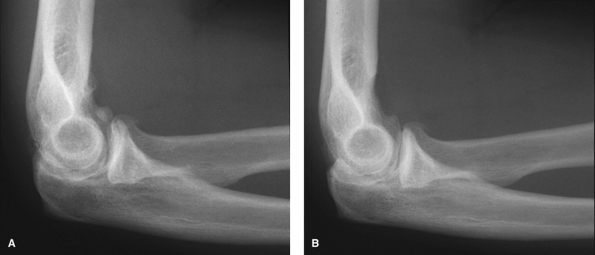

![]() |

Figure 62-8 A:

Preoperative radiograph of a typical patient, a 47-year-old right hand–dominant man with right elbow osteoarthritis, demonstrates osteophyte formation and joint space narrowing. B: Postoperatively, the osteophytes and bony spurs have been removed. |

anterior and posterior aspects of the elbow joint can be visualized and

pathology addressed (Fig. 62-8). To obtain a